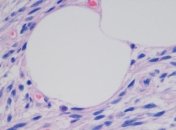

Исследователям удалось полностью воссоздать внешний слой кожи грызуна